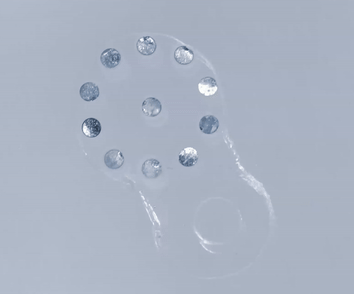

Bioabsorbable Sticker由水凝膠和微小金屬片材料制備,擁有三種不同類型,以適用于胃、腸和胰腺的吻合口滲漏監(jiān)測(cè)。Bioabsorbable Sticker尺寸從4mm到12mm。

Bioabsorbable Sticker被制成柔軟的微小貼紙形狀。當(dāng)Bioabsorbable Sticker植入到吻合口處時(shí)會(huì)隨著身體 pH 值變化而改變形狀,這樣就可以對(duì)胃腸手術(shù)之后并發(fā)癥(例如吻合口滲漏)進(jìn)行早期預(yù)警。臨床醫(yī)生可以通過(guò)超聲成像實(shí)時(shí)查看Bioabsorbable Sticker形狀變化。

Bioabsorbable Sticker當(dāng)接觸到 pH 值異常高或低的液體時(shí),就會(huì)在幾分鐘內(nèi)改變形狀(當(dāng)遇到酸性液體(例如胃酸)時(shí)就會(huì)膨脹,當(dāng)遇到腐蝕性液體(例如胰液)時(shí)就會(huì)收縮)。

之所以Bioabsorbable Sticker能夠在超聲下看得見(jiàn),主要Bioabsorbable Sticker上微小金屬片會(huì)隨著凝膠形變,聚集或者分散。超聲就根據(jù)微小金屬片聚集或者分散來(lái)判斷胃腸、胰腺的吻合口是否發(fā)生泄漏。